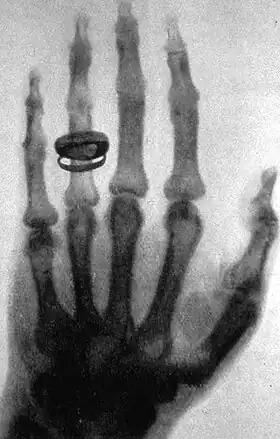

An X-ray picture (radiograph), taken by Wilhelm Röntgen, of his wife's hand

• X-rays. A form of electromagnetic radiation with a wavelength in the range of 10 to 0.01 nanometers, corresponding to frequencies in the range 30 to 3000 PHz (1015 hertz). X-rays are primarily used for diagnostic medical and industrial imaging as well as crystallography. X-rays are a form of ionizing radiation and as such can be dangerous.